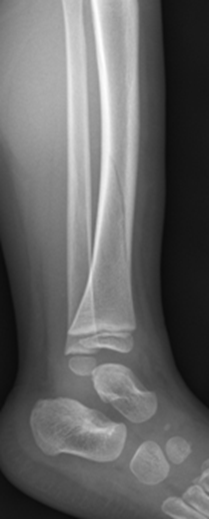

Salter Harris I fracture of fibula

- No formal follow up required.

Undisplaced Salter Harris II fracture of fibula

- Follow up GP 7-10 days for repeat X-ray.

- If displaced, not suitable for CAM Boot.

Undisplaced epiphyseal fracture of distal fibula